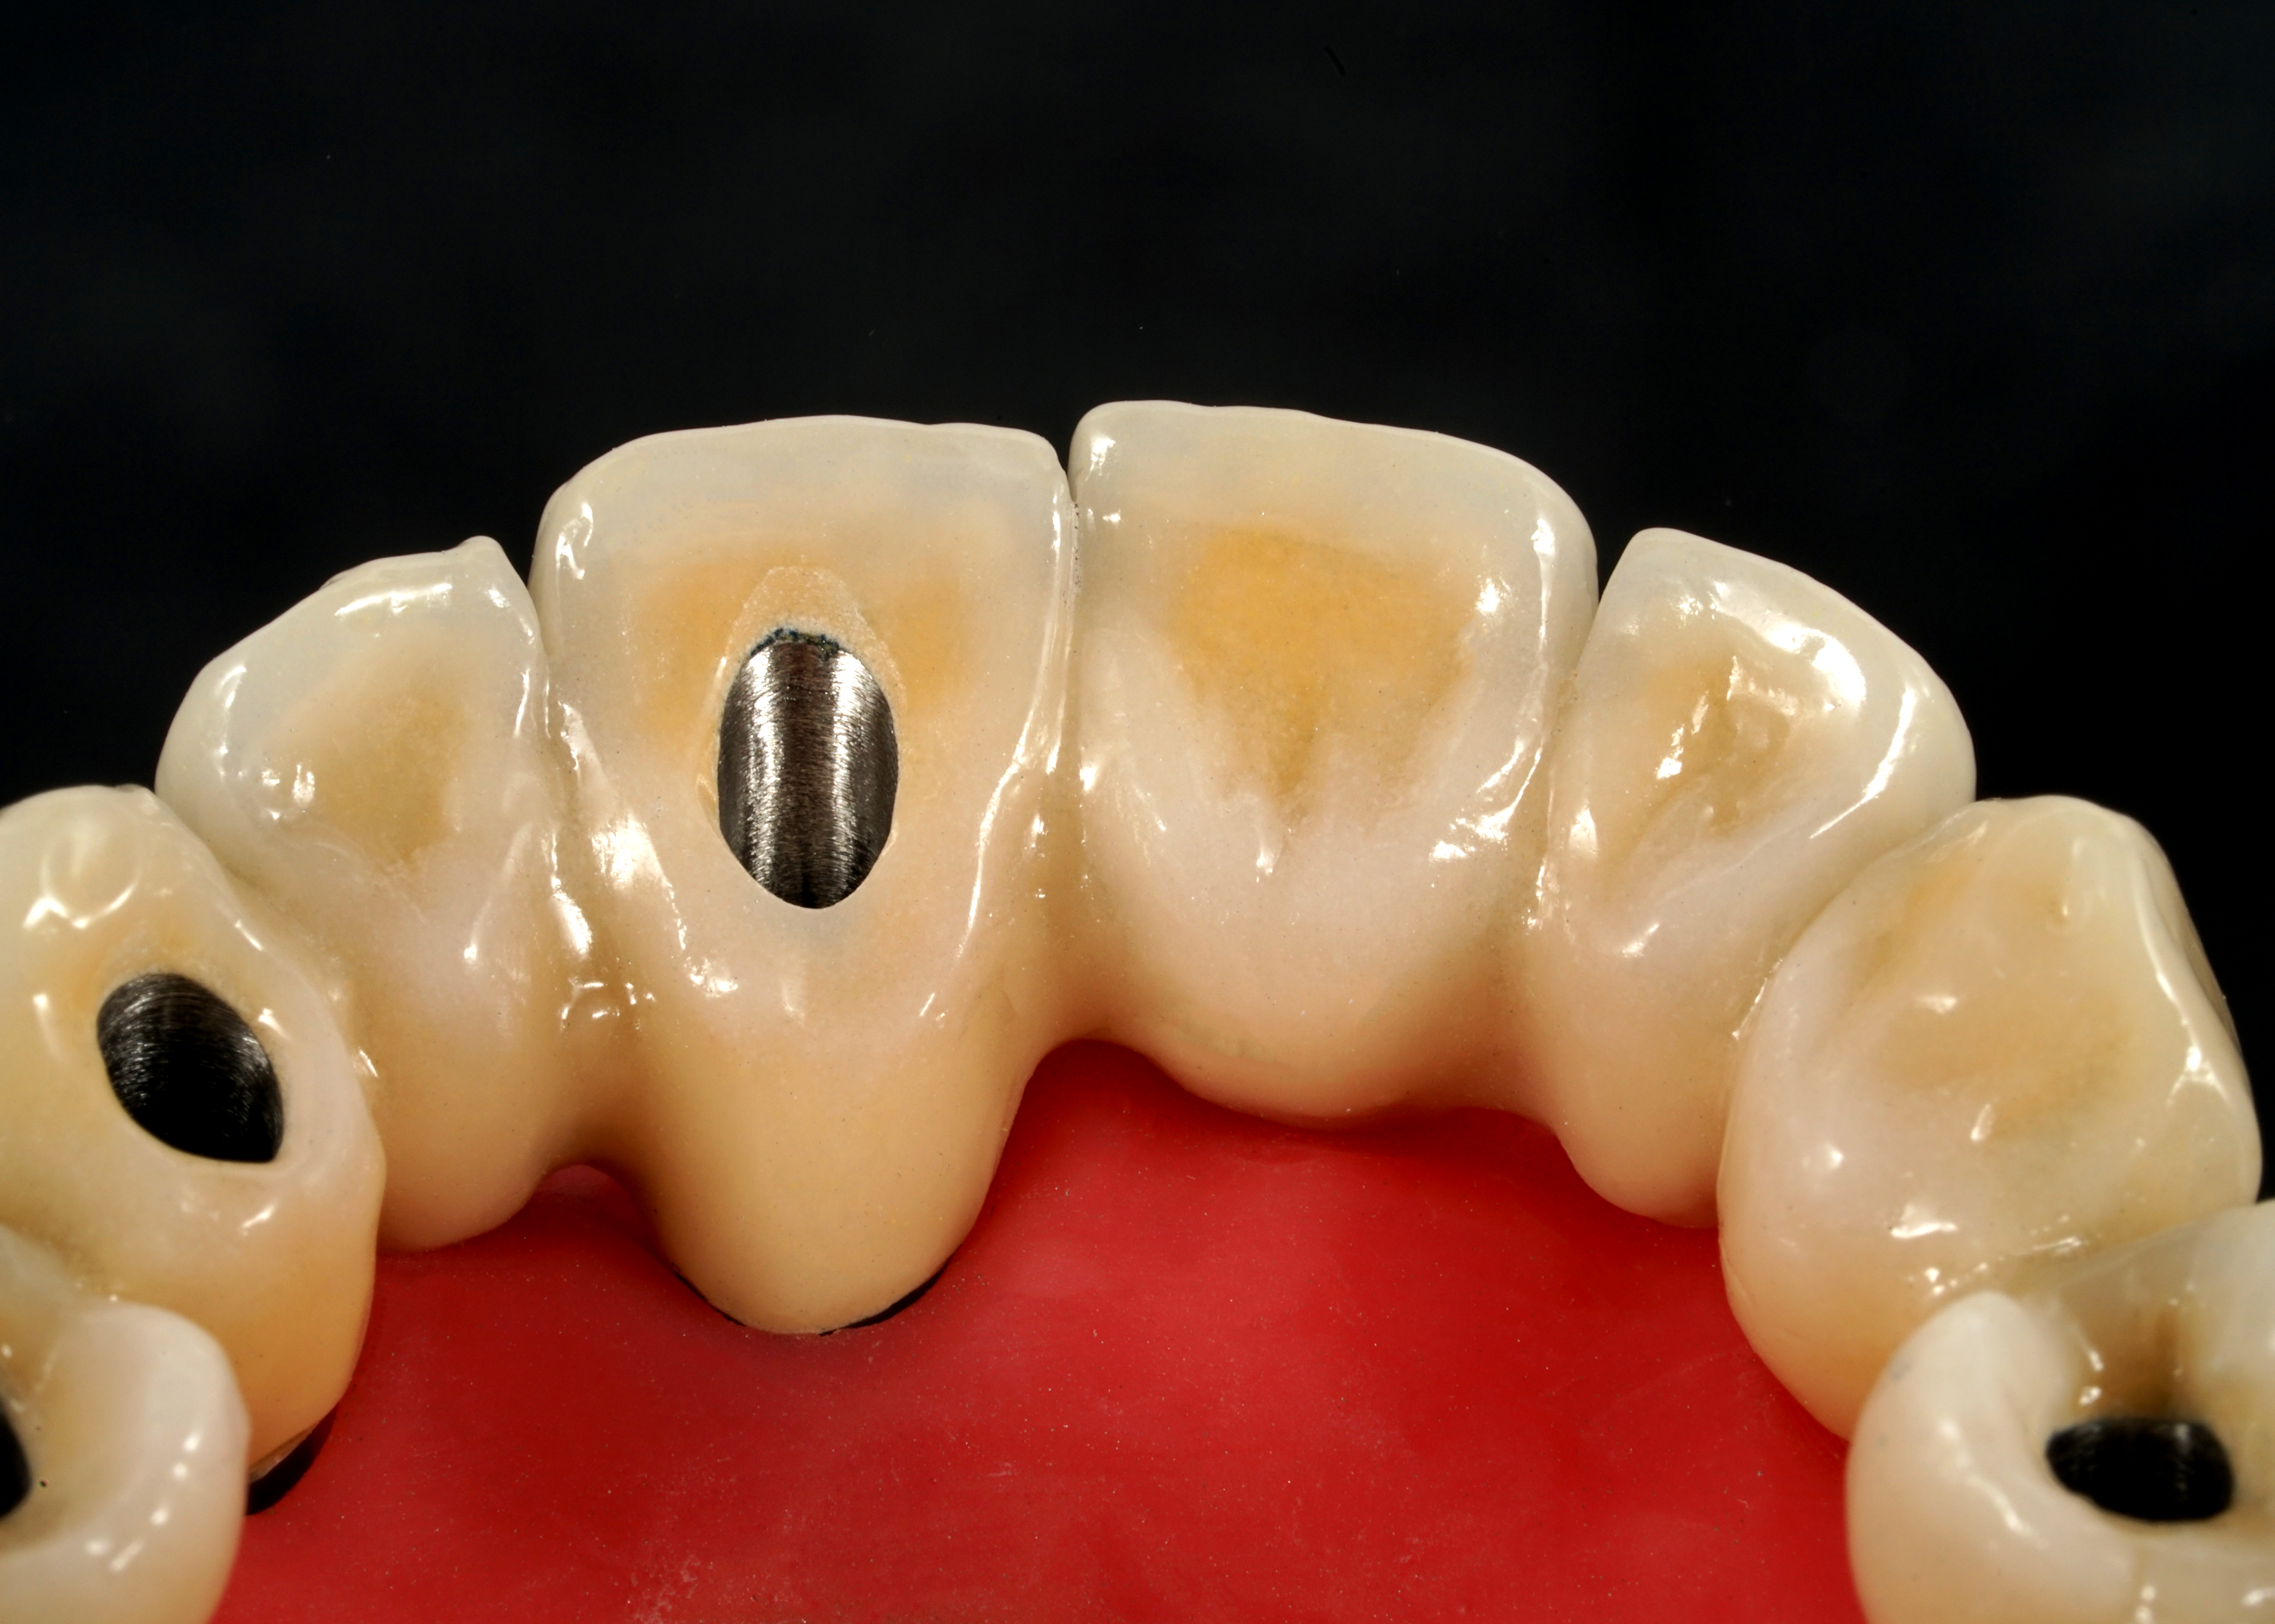

La parte di ceramizzazione è stata affidata ad una solida certezza interna al nostro laboratorio DentOne: Fabrizio Pasini, il quale ha espresso il suo sublime gusto estetico stratificando ad arte una base in CoCr con ceramica Shofu (Fig. 17, 18, 19, 20, 21).

Fig. 18. Vista palatina della ceramizzazione del gruppo frontale e degli accessi vite con foro inclinato